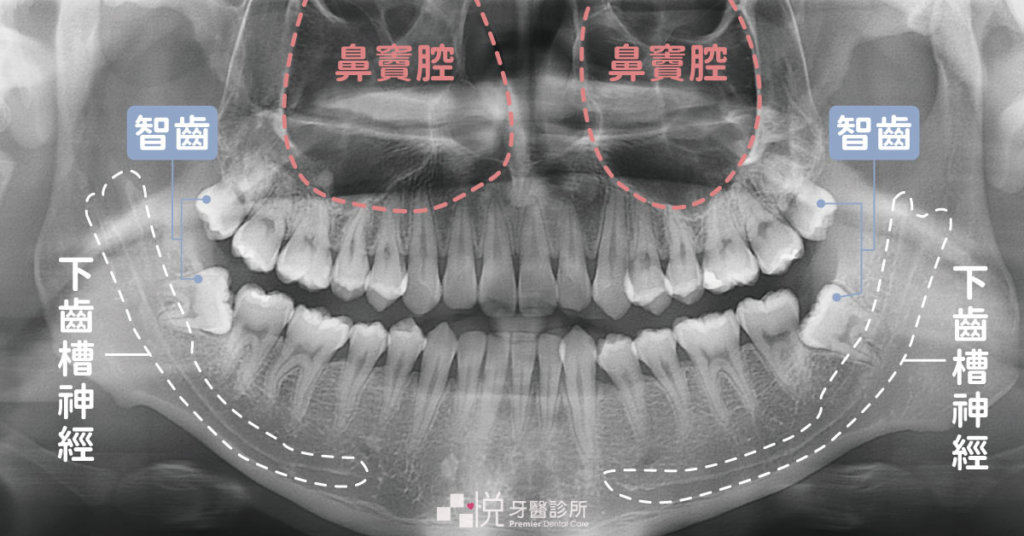

而上顎智齒最常遇到的就是口鼻竇相通,因為智齒比較靠近上顎竇,雖然多數時候拔牙當下不會造成穿孔,但術後回去吸管吸飲料也有可能產生穿孔,或是原本感染較嚴重的智齒也可能產生自發性的口鼻竇相通,如果有這樣的情況是必需要經過手術修補處理。

下顎智齒最常遇到的風險則是下齒槽神經或舌神經受傷,智齒的牙根尖往往都會緊貼著下齒槽神經,儘管拔牙時手術器械不會直接傷到神經,但牙齒脫離齒槽時或是拔完的傷口血塊,都有可能會造成神經受損,統計上發生率佔0.35 ~ 8.4 %,而導致暫時的嘴唇臉頰麻木感,96 %的患者會在三個月內逐步恢復,但統計上仍有 < 1 % 神經受損的患者會有永久損傷。[1]